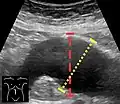

Aortic measurement on abdominal ultrasonography in the axial plane between the outer margins of the aortic wall[39]

Ultrasonography in the sagittal plane, showing axial plane measure (dashed red line), as well as maximal diameter (dotted yellow line), which is preferred